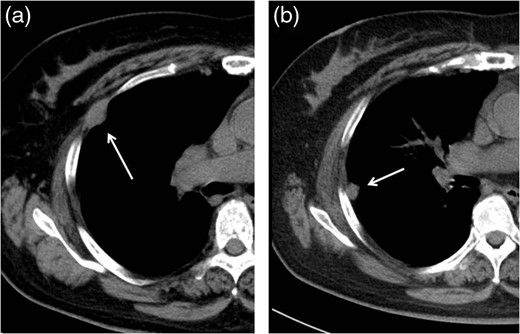

Follow-up CT performed 36 months after the operation revealed two pleural tumors located near the second and third ports (Fig. 2a and b). We suspected the pleural recurrence of thymoma and performed a second operation. Initially, the operation was performed only by VATS with three ports. After removing the severe adhesion between the lung and chest wall, we were able to identify the two tumors. As with the extrapleural tumor, the tumors arose from the intercostal space. Their surfaces were covered with parietal pleura with partial irregularity (Fig. 3). There were no other recurrent findings in the thoracic cavity. Given these findings, we diagnosed these tumors as port-site implantations after the first VATS.

Follow-up CT at 36 months after the operation revealed two pleural tumors locating at the second (a) and third (b) ports used in the VATS operation.